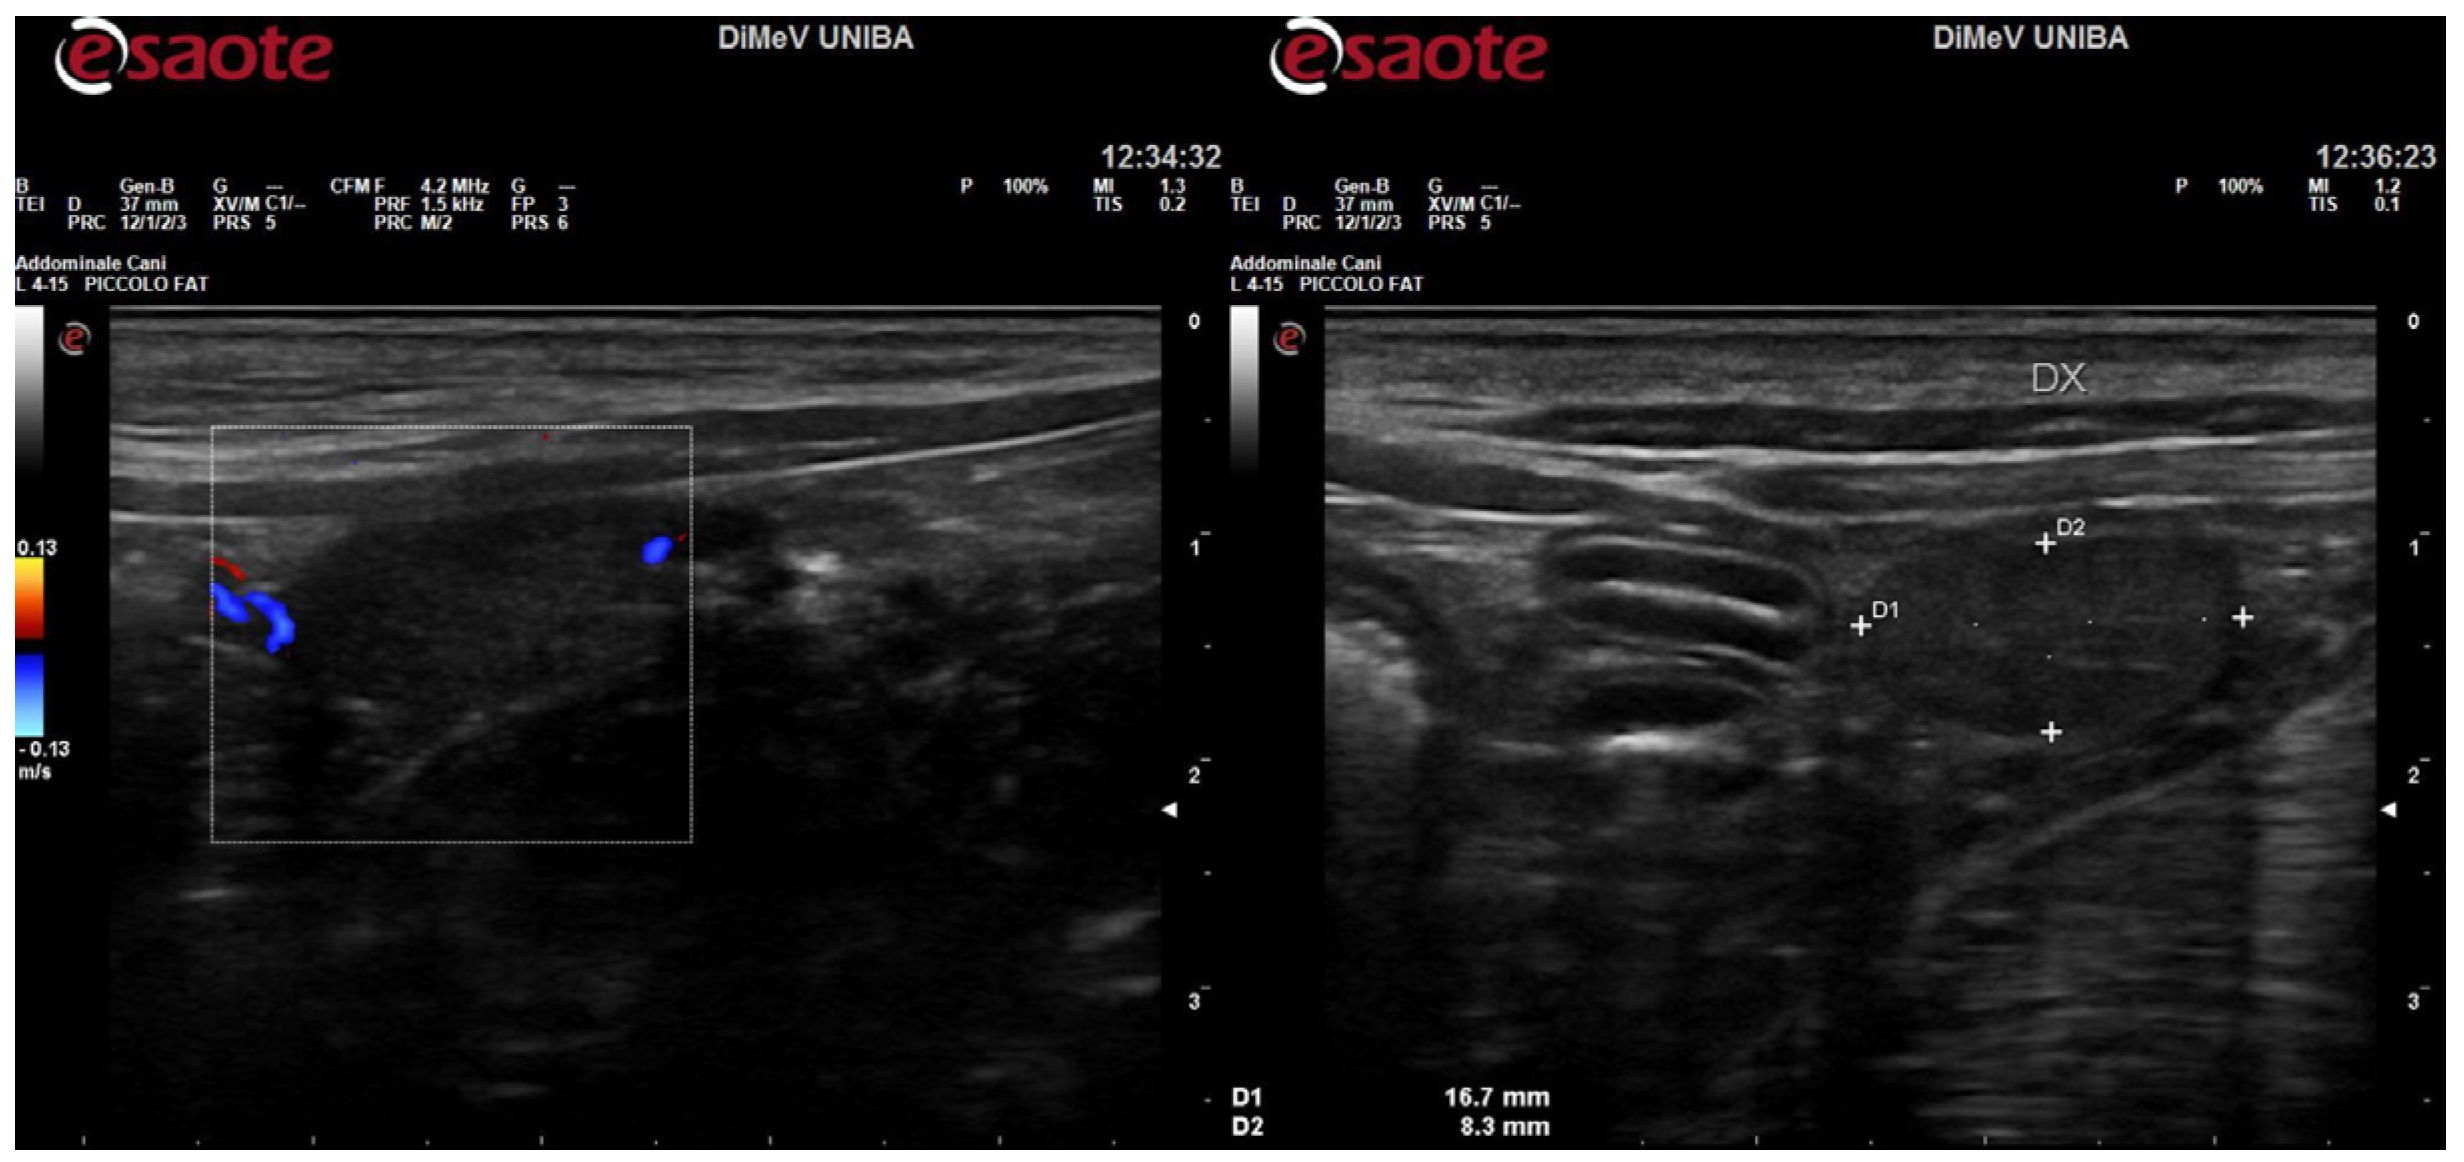

Additionally, imaging tests were performed using an Esaote MyLab Alpha device (Figure A2) and computed tomography (CT) (Figure A3). This advanced diagnostic examination was carried out on a multi-slice CT scanner (Sensation 16) with iodine contrast medium (370 mg/mL) at a dosage of 800 mg iodine/kg.

Figure A2.

Ecographic study of the testicle-like abdominal structure using color Doppler and in B-Mode.